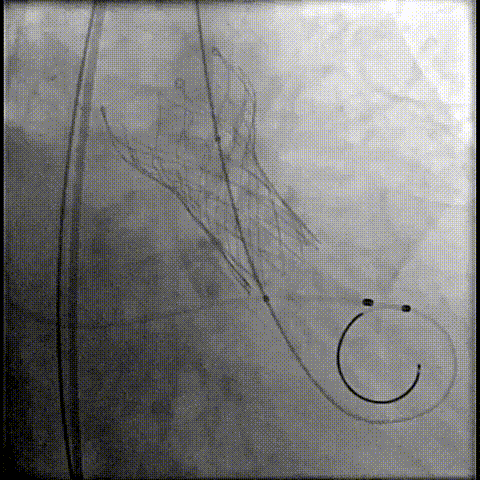

23球囊后扩

最终造影形态位置良好,轻微瓣周漏

术后压差降为0mmHg

轻松过弓,精准可控:该病例弓角小,在未使用snare的情况下,轻松完成过弓,通过性能得到了很好的验证;

精准释放:该病例室间隔膜部较短,需精准释放到位,减少PPI发生可能性;其底部桶状设计更易迅速锚定,协同释放张力小,助力最终精准释放;